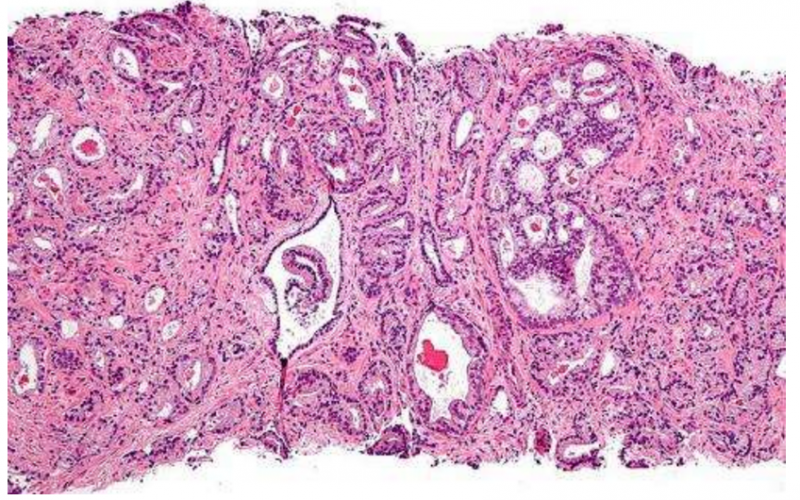

美国约翰斯·霍普金斯大学医学院Guedes等报告,错配修复(MMR)2蛋白的缺失与MSH2基因的失活和超突变、肿瘤淋巴细胞浸润密度大均有关,在高级别前列腺癌中更常见。(Clin Cancer Res. 2017; doi: 10.1158/1078-0432.CCR-17-0955.)MMR基因的失活可能预示转移性前列腺癌对免疫治疗敏感性。该研究共纳入113